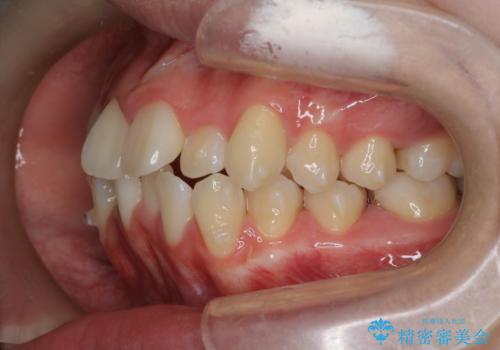

【インビザライン】前歯の凸凹を非抜歯で治療

- 前歯の凸凹を主訴の来院されました。

奥歯を後ろの方に移動させるために矯正用のアンカースクリューを使いながら治療をおこないました。

患者さんの都合により、マウスピースの装着時間が不足したため、途中からワイヤーにて治療を行いました。

インビザラインは20時間以上の装着は必要となるため、患者さんによってはワイヤーの方が向いていることがあります。